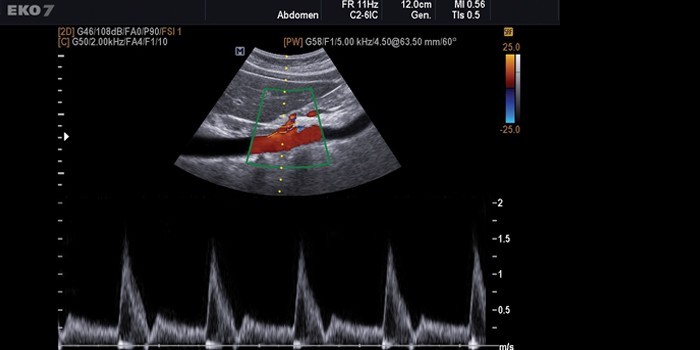

При проведении УЗДС на монитор транслируется двухмерное цветное изображение исследуемого сектора конечности. Плюсы методики – объективность результатов, возможность получить данные о структурных изменениях в стенках. В реальном времени фиксируются фоновые и индуцируемые показатели кровотока, проводится проверка кровеносных периферических систем. Методика выясняет причины непроходимости системы кровообращения, дает информацию о клапанах вен.

Триплексное сканирование

УЗИ сосудов нижних конечностей этого типа самое быстрое по времени, точное, но цена на него выше, чем на остальные. Оно расширяет возможности дуплексного, добавляя режимы цветного допплера, т.е. цветного изображения движения крови в сосудах, по которому более наглядно можно судить о направлении кровотока и его скорости, а также позволяя более точно оценить проходимость сосудов и степень стеноза. Достигаются три цели, что и определило название метода – триплекс:

- исследуется анатомия сосудов;

- оценивается кровоток;

- производится точная оценка проходимости сосудов в цветовом режиме.